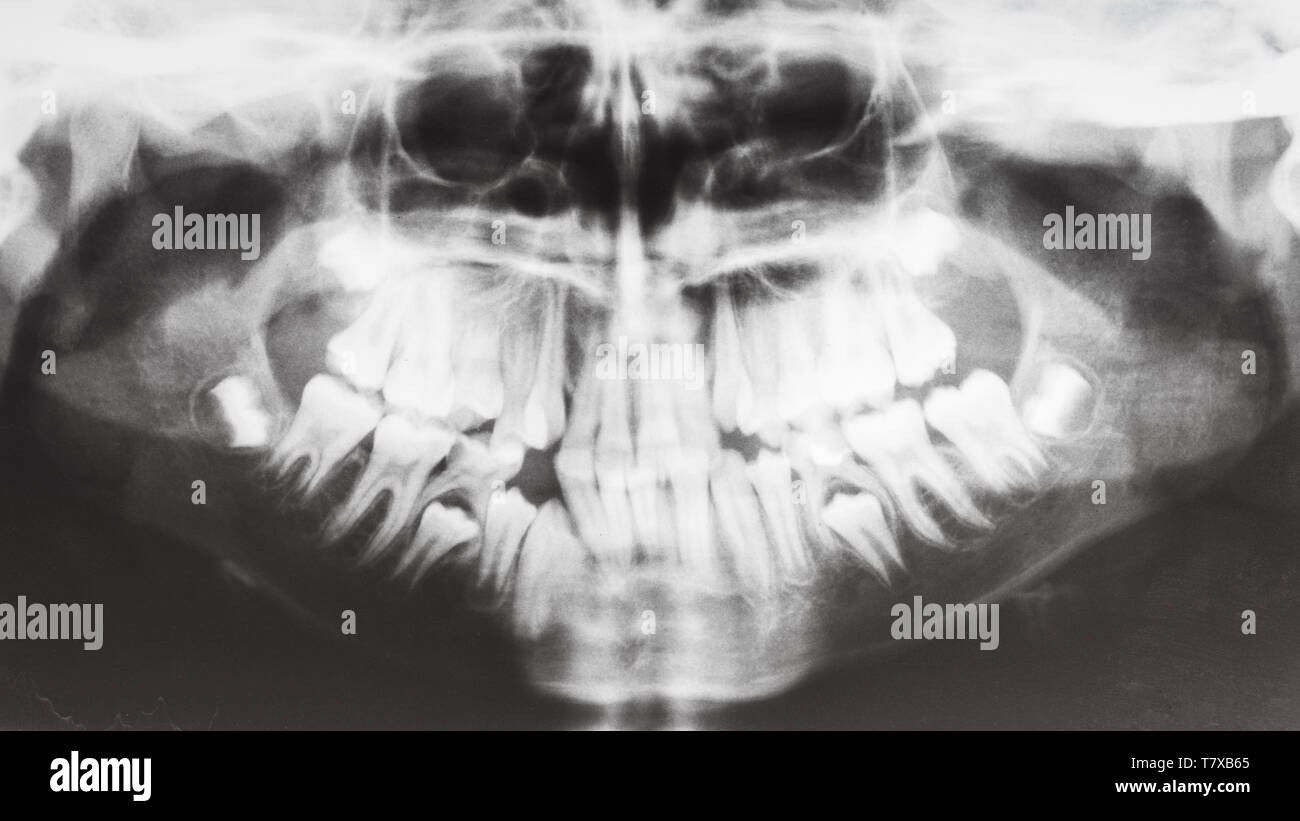

From www.alamy.com

front view of human jaws on Xray image Stock Photo Alamy Jaw X Ray Views The temporomandibular joint (tmj) is an atypical synovial joint located between the condylar process of the mandible and the mandibular. Proper characterization of jaw abnormalities is essential to ensure appropriate patient care and reduce morbidity. This projection is useful in identifying structural changes and displaced fractures of the mandible in a trauma setting, and in neoplastic or inflammatory changes. The. Jaw X Ray Views.